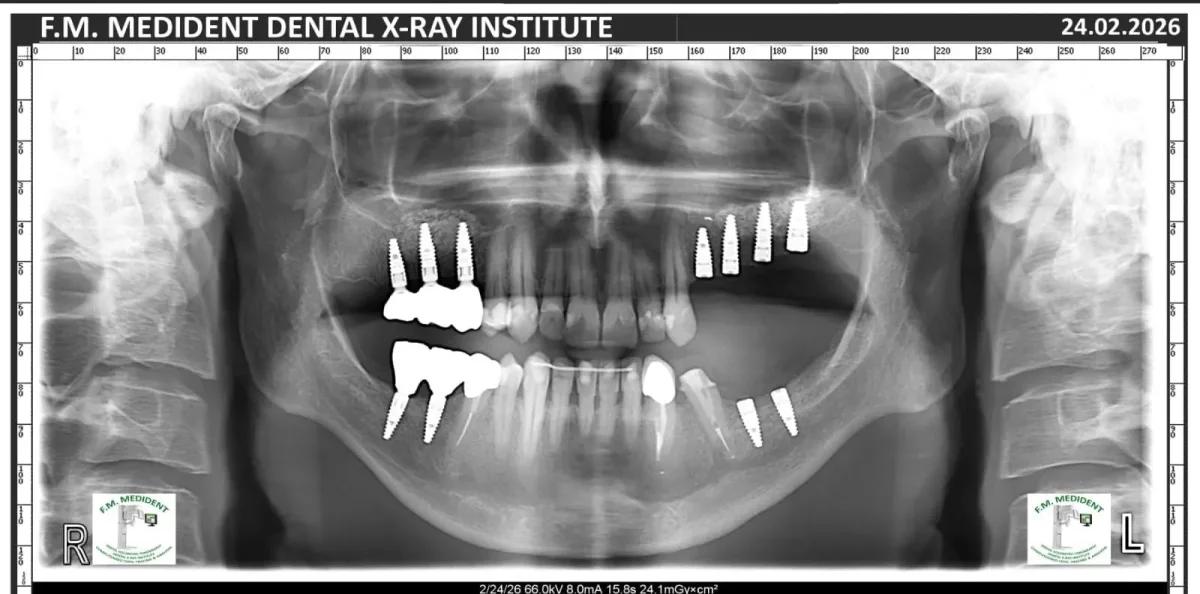

Cazuri reale înainte și după, din tratamente realizate în clinică.

Înainte

DupăExemple reale din cazuri tratate în clinică.